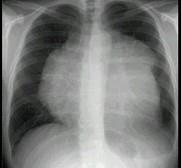

男,8岁,胸闷,气急,查体见颈静脉显露,胸片如图,最可能的诊断是 ( )A.心包积液B.心肌炎C.淋巴瘤D.房间隔缺损E.肺静脉异位引流

问题 男,8岁,胸闷,气急,查体见颈静脉显露,胸片如图,最可能的诊断是 ( )

选项 A.心包积液 B.心肌炎 C.淋巴瘤 D.房间隔缺损 E.肺静脉异位引流

答案 C